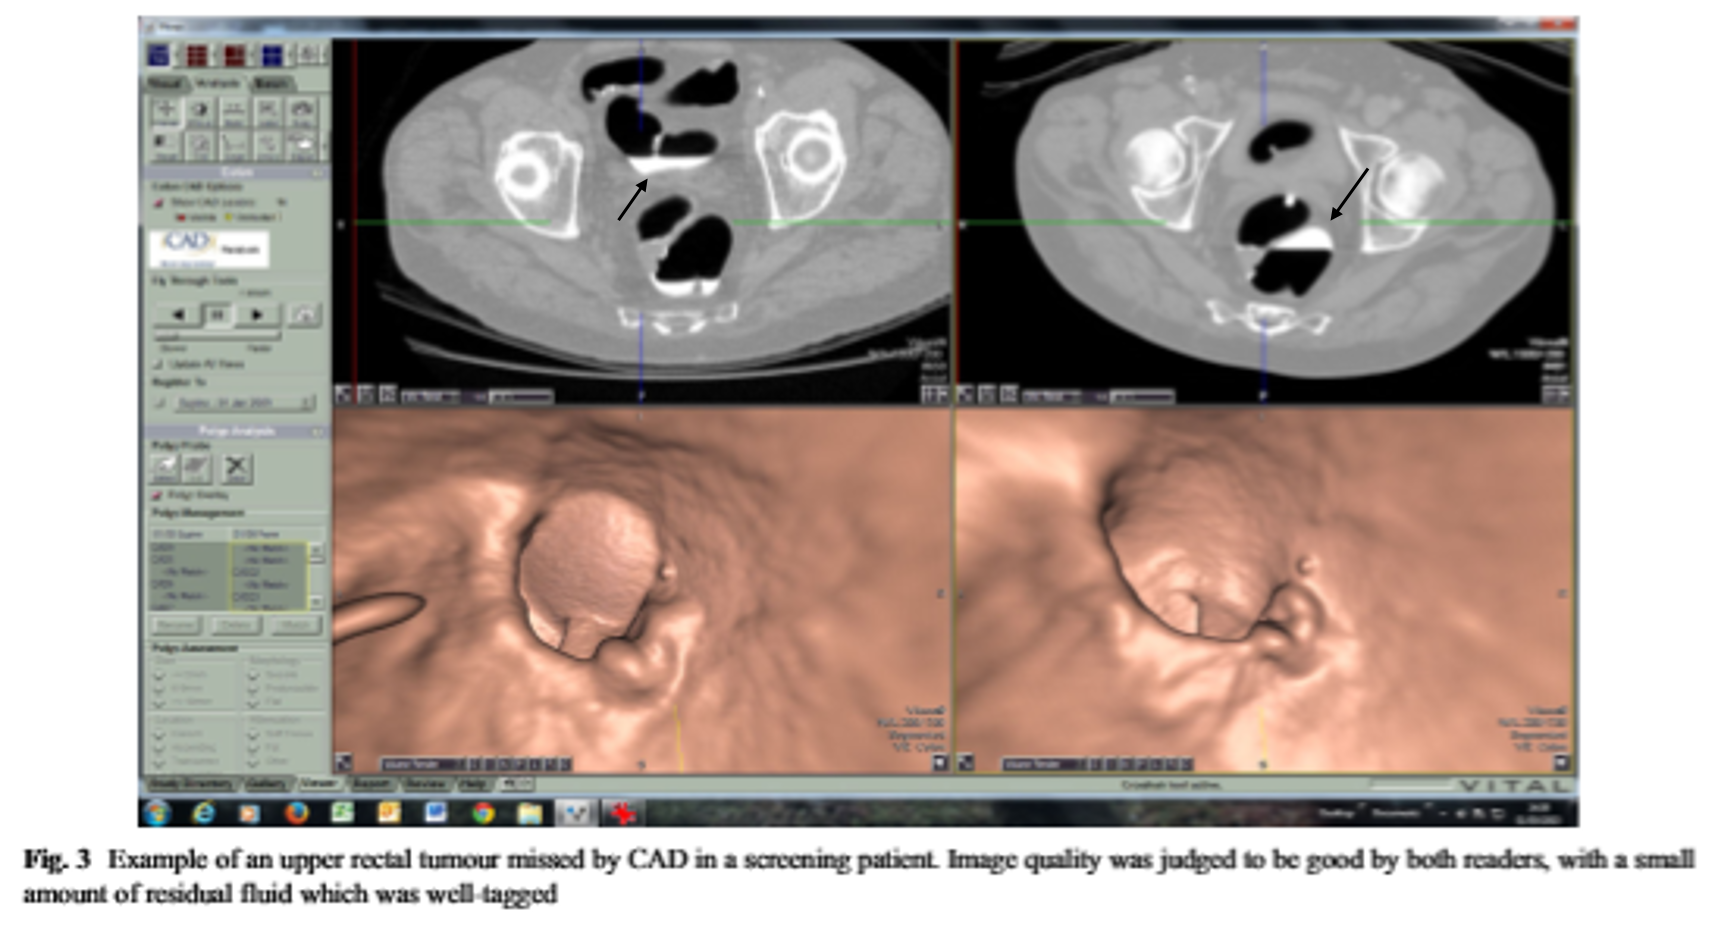

In the above CT image, a black arrow indicates the tagged fecal materials(interfering image reading) with contrast agent. These are automatically excluded and 3D images are reconstructed.

Especially, one of the most important aspects of image interpretation is cleaning of the colon. Remaining fecal materials are similar to a polyp and can be diagnosed as false positive. Water in the colon is excluded from the image during reconstruction and may result in false negative. Cleaning the colon is the same as for colonoscopy.

Usually, about 4 liters of polyethylene glycol is taken on the day before the test. Recently, a small amount of contrast agent is taken to differentiate water or remaining feces. They are distinguishable because it looks white due to contrast agent. This process is called “Fecal Tagging”.